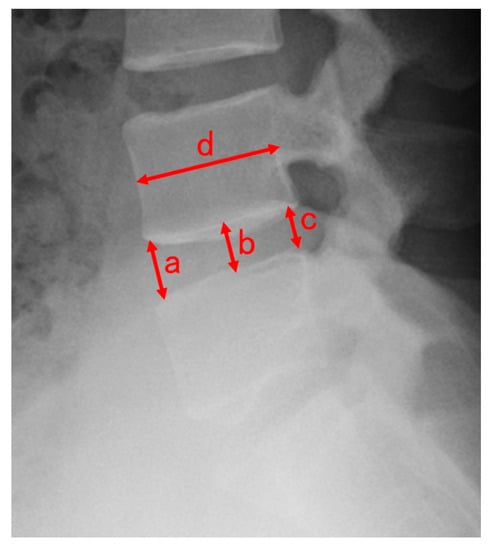

- Inoue, H.; Ohmori, K.; Miyasaka, K.; Hosoe, H. Radiographic evaluation of the lumbosacral disc height. Skelet. Radiol. 1999, 28, 638–643. [Google Scholar] [CrossRef]